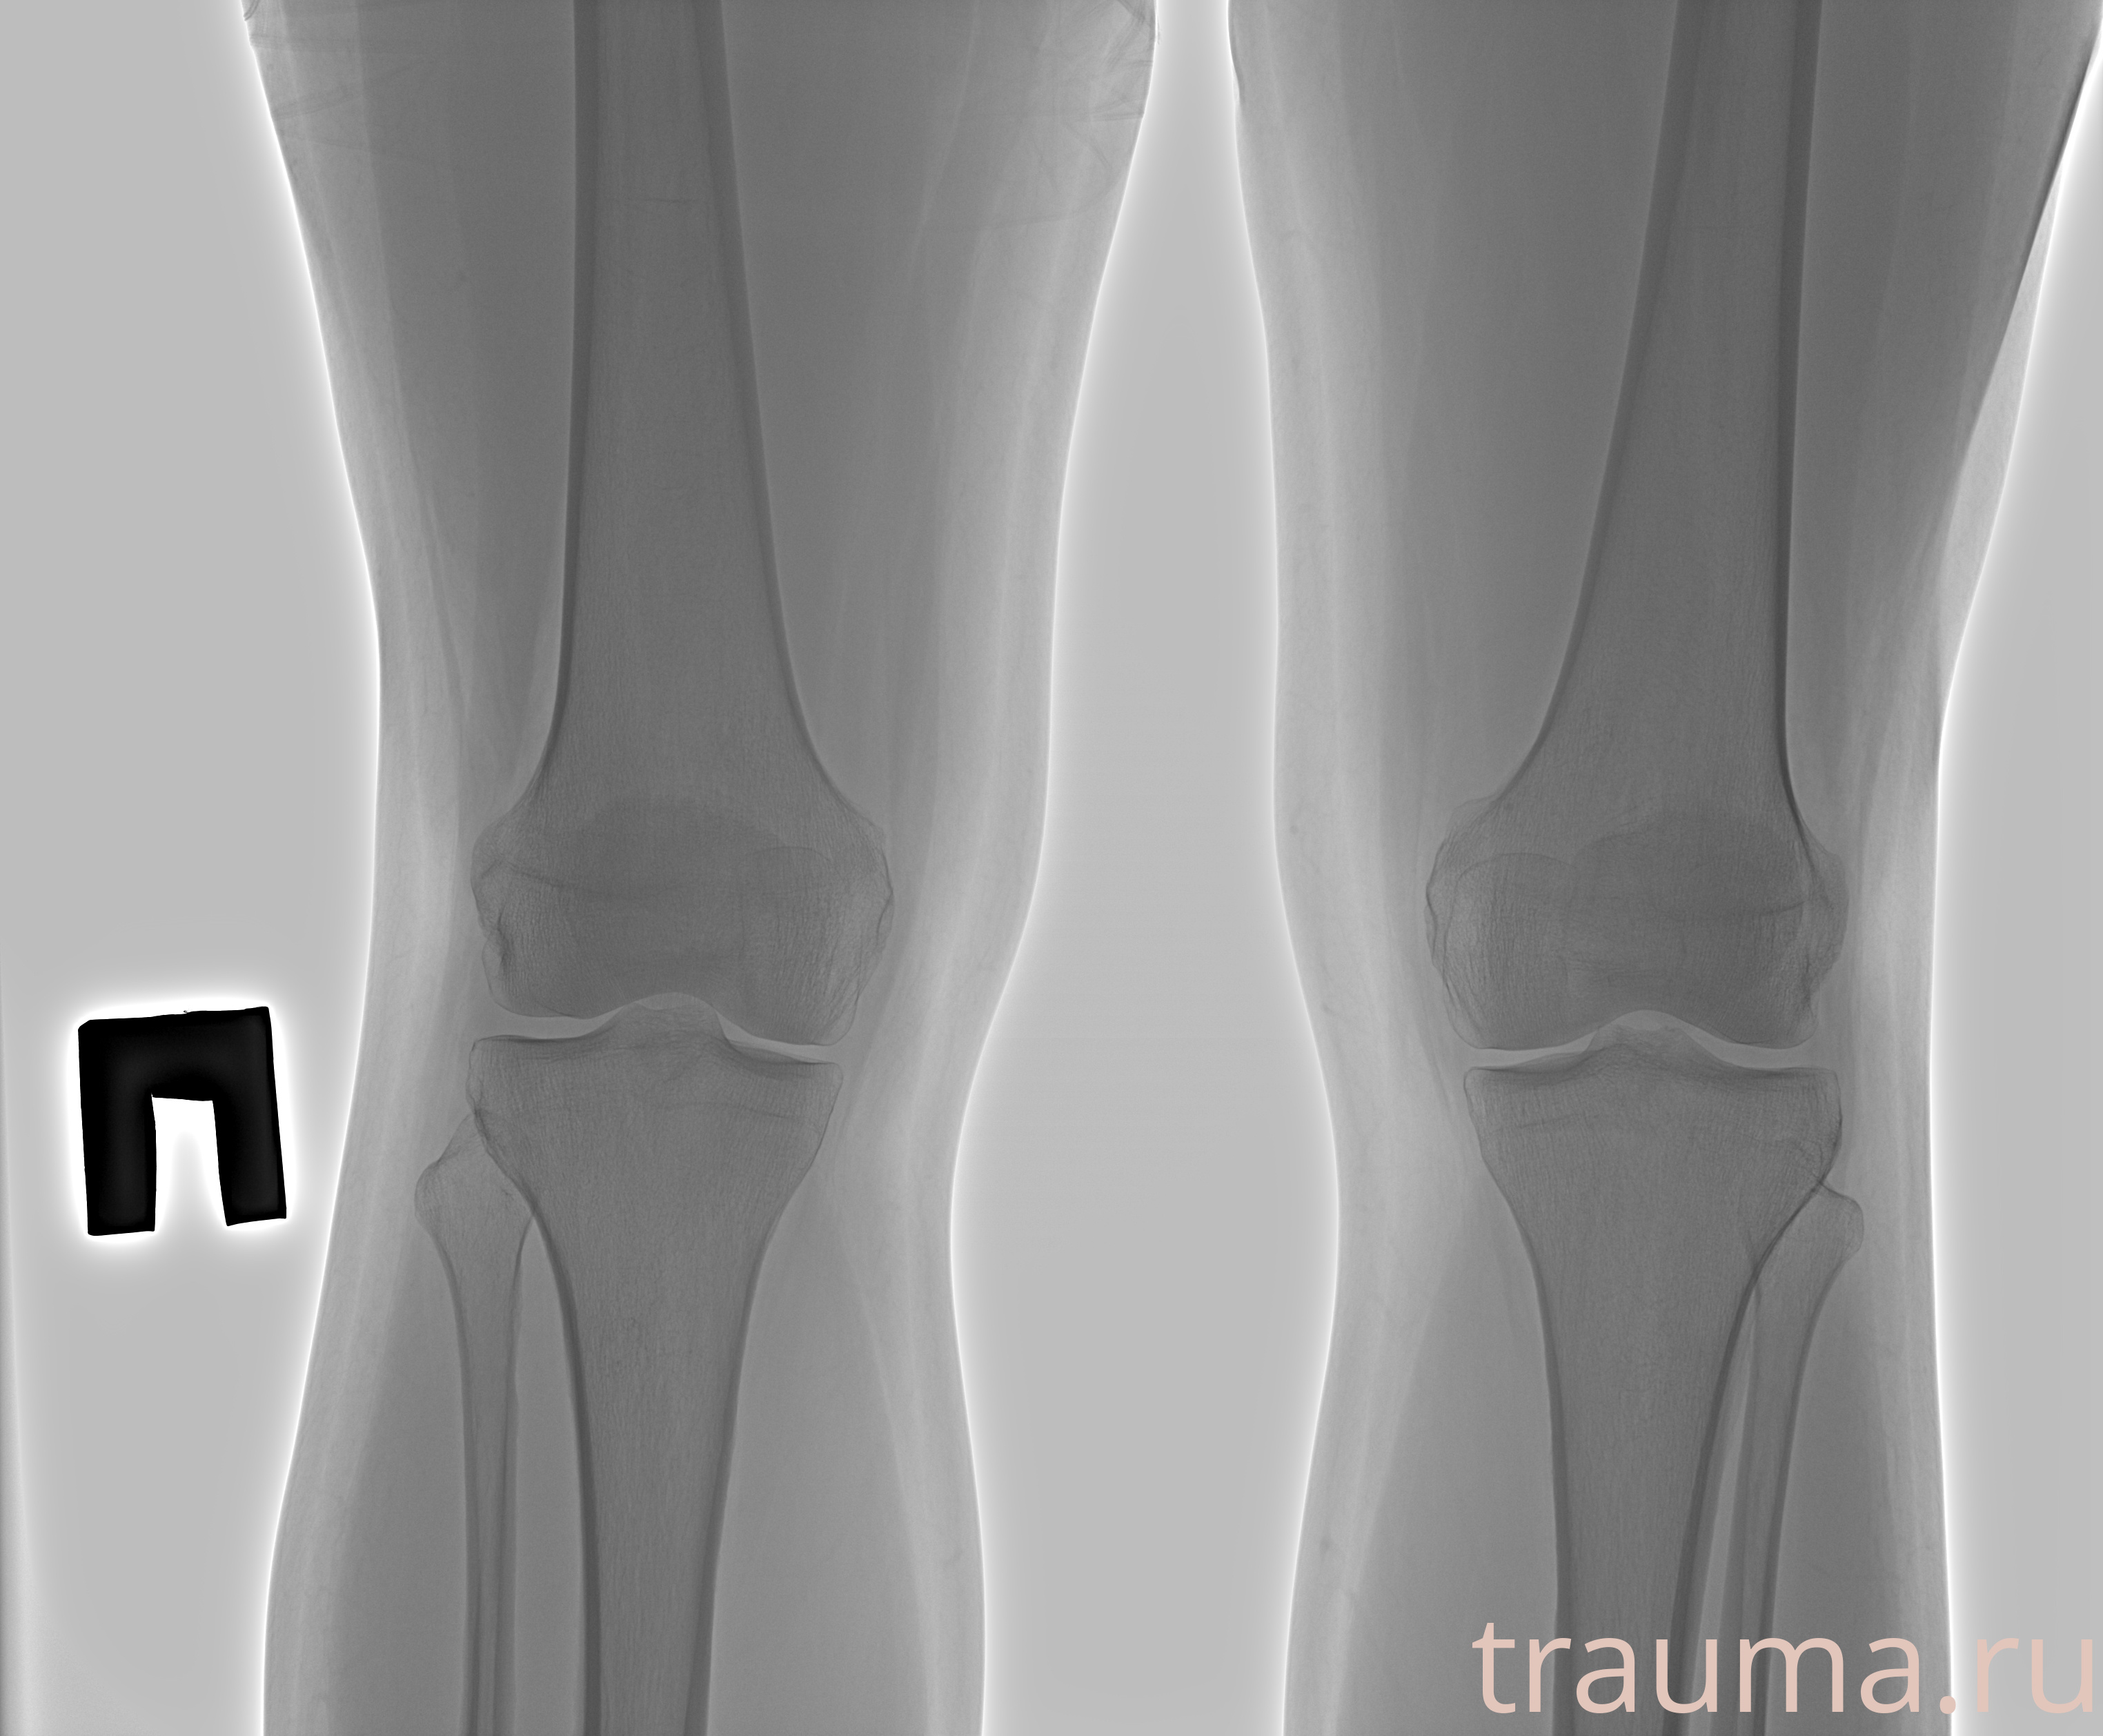

Рентгенограммы

Рентген на дому: по вашему адресу приезжает врач-рентгенолог, травматолог-ортопед с мобильным рентгеновским аппаратом, проводит диагностику травмы или заболевания, делает необходимые рентгенограммы, дает рекомендации по дальнейшему лечению. Получить качественные снимки в домашних условиях возможно благодаря уникальной методике, разработанной МосРентген Центром для института  Склифосовского